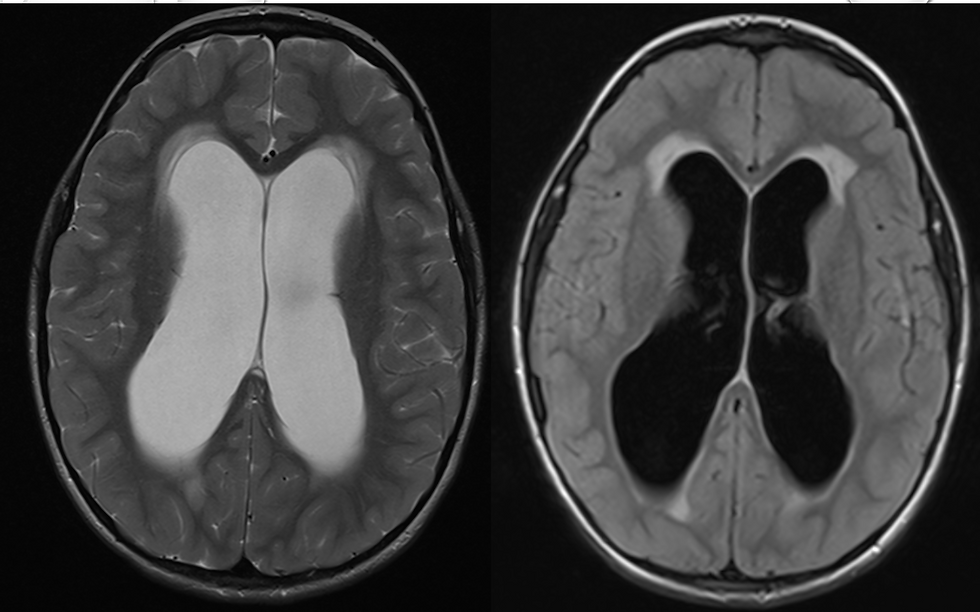

Congenital malformations: Conditions present at birth, such as spina bifida or hydrocephalus.

A young patient diagnosed with hydrocephalus underwent a minimally invasive procedure to insert a shunt. This intervention significantly improved the child's quality of life, allowing for normal development and activities.